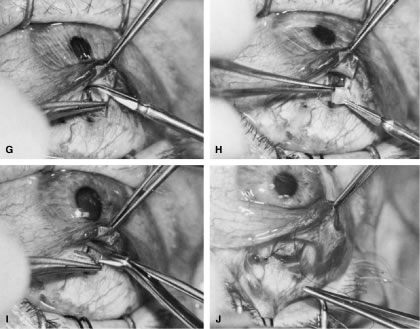

If the decision has been made to perform surgery, the surgeon must consider how to perform the surgery to achieve the desired target pressure range (see Table 14). Although it is not always possible to achieve the desired target pressure range, certain procedures and approaches to surgery give the surgeon the ability to approximate the goal. A guarded filtration procedure performed essentially as described by Watson, for example, in a white patient without risk factors for failure usually will result in IOP of approximately 17 mm Hg, ranging from 15 to 19 mm Hg.26 In contrast, a full-thickness filtering procedure, such as a corneoscleral trephine, usually will result in a mean IOP of approximately 14 mm Hg, with a range of 12 to 16 mm Hg.26

To obtain increasingly lower IOP, it is necessary to modify surgical technique (Table 15). By performing guarded filtration procedures so that the sutures can be released postoperatively, with the use of either laserable or releasable sutures, a lower final IOP can be obtained in some cases. This technique allows a bleb to develop that is similar to that seen in a full-thickness filtration procedure. Such blebs tend to be thin, polycystic, and located directly at the limbus, in contrast to those seen after classic trabeculectomy, which are thicker, lower, more diffuse, and more posterior. When antifibrosis agents (antimetabolites and corticosteroids) are added to procedures designed to develop full-thickness filtration, IOP tends to be sharply reduced.27–29 The blebs associated with the use of 5-fluorouracil (5-FU) and mitomycin are an exaggeration of the full-thickness type of bleb: Often, they are extensive, sometimes involving 360 degrees of the anterior surface of the globe, and the conjunctiva tends to be thin and completely ischemic.30–34

Table 15. Methods Thought to Help Achieve Lower Final Intraocular Pressure After Filtration Procedure

Antimetabolites

Topical corticosteroids (up to equivalent of prednisolone 1% 4 times daily)

Minimal overlap of scleral flap (minimal guarding)

Nasally placed bleb

Use of releasable or laserable sutures in scleral flap

Thin scleral flap

The thin filtration blebs associated with the use of mitomycin or 5-FU may rupture spontaneously. They tend to be so high that the adjacent cornea becomes dry, with the development of an uncomfortable delle. Ptosis tends to develop, and patients often are photophobia One of the most serious concerns is the high incidence of endophthalmitis in patients with thin blebs. When full-thickness blebs were the routine type of glaucoma procedure, endophthalmitis would develop in approximately 1% of patients. When 5-FU was used to develop filtration blebs inferiorly, an 8% rate of endophthalmitis was reported.35–42 Hypotony, even in the absence of a thin bleb, introduces serious problems. The soft eye does not maintain a constant optical state, and it has a constantly changing amount of astigmatism that makes it impossible to correct. Each time the patient blinks, the amount of astigmatism changes. Macular and disc edema cause reduced central acuity and deterioration of the visual field, and the globe may have a constant, visceral ache. Patients with such eyes are not comfortable.